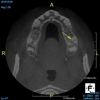

(6.) A lateral cyst associated with tooth No. 12 was asymptomatic and misdiagnosed on a periapical radiograph, but it was correctly diagnosed thanks to this CBCT slice of the maxilla that isolates the lesion.

Figure 6

Being able to see the number and shape of the canals accurately prior to treatment is the desire of any clinician who performs endodontics. Research suggests that, due to improved diagnostic accuracy, the final treatment plan may change in up to 50% of endodontic cases if CBCT is used rather than traditional 2D imaging.14,15 The question of whether or not a patient has an MB2 canal can be answered prior to opening the access preparation (Figure 4 and Figure 5). Visualizing single canals that bifurcate in the apical or middle third of the root or those that merge to a single apical opening can help clinicians to understand their instrumentation needs in advance. In addition, the ability to measure the length and shape of a canal planned for instrumentation prior to utilizing an apex locator helps to confirm any measurements obtained by other means. It should also be noted that the ability to see a pathosis in 3 dimensions and to involve the patient in understanding his or her condition prior to any decision-making allows for definitive treatment planning. In fact, many patients have pathoses associated with teeth that are asymptomatic that remain unknown to them until they are visually presented with the evidence (Figure 6).